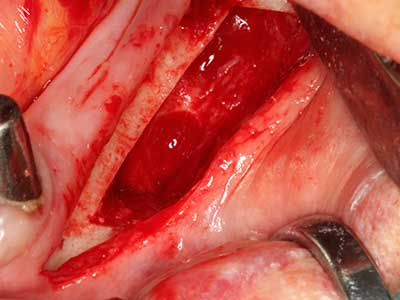

Bone tissue is not simply a mineral structure but also contains a substantial proportion of collagen fibres. This means it not only has good compressive strength but also a degree of flexibility, which can be taken advantage of when performing bone augmentations. In the classical expansion procedure using bone splitting, the atrophied alveolar ridge is split longitudinally and carefully expanded after reaching an adequate osteotomy depth (Fig. 13-16), ideally without substantial removal of the periosteum (Brugnami, Caiazzo et al. 2014, Stricker, Fleiner et al. 2014). Screw and plate systems with increasing expansion distance have proven effective in separating the two bone lamellae while remaining below the fracture threshold. In general, residual bone widths of at least 3–4 mm are required (Chiapasco, Zaniboni et al. 2006) to guarantee adequate flexibility and sufficient bone coverage of the future implants. If necessary, a vertical relief osteotomy on one or both sides can improve flexibility. A combination with additional augmentation techniques, particularly on the buccal side, has been described as an alternative to the classical technique.

The splitting procedure is particularly atraumatic and there is no significant loss of dimension when using piezosaws, and there are no significant differences between implants in split jaws and implants in an alveolar ridge without a bone deficit (Chiapasco, Zaniboni et al. 2006, Danza, Guidi et al. 2009). However, sufficient continuous irrigation is essential, particularly with locally restricted and deep splitting to prevent thermal stress in the apical osteotomy regions.